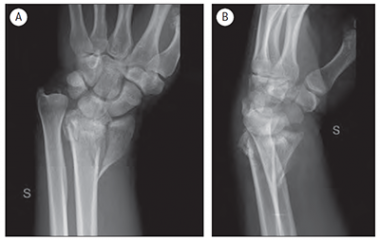

41 gadu vecam pacientam ar augstas enerģijas traumu pirms ārstēšanas uzsākšanas veikta rentgenogramma (sk. 5. A, B att.). Traumas dienā veikta lūzuma fiksācija ar ĀFA (sk. 6. att.), pēc piecām dienām – lūzuma osteosintēze ar volāro kompresijas plāksni un stieplēm plaukstas artroskopijas kontrolē (sk. 7., 8. att.). Pēcoperācijas rentgenogrammā redzama locītavas virsmu kongruences restaurācija abās standarta projekcijās (sk. 9. A, B att.).

5. attēls. Rentgenogramma traumas dienā / | 6. attēls. Rentgenogrammā – aina pēc ĀFA uzlikšanas / X-ray after external fixation |

9. attēls. Pēcoperācijas rentgenogrammas / X-ray after the surgery